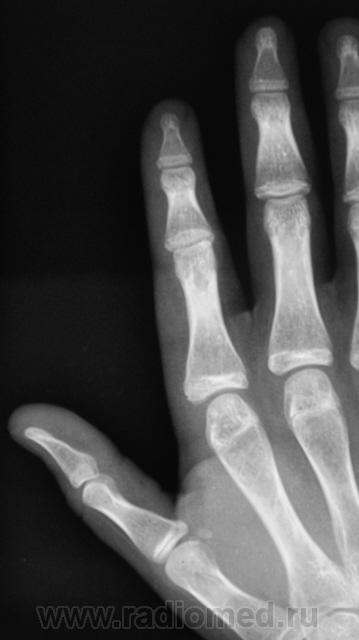

Судя по-всему тип роста экспансивный ,симпотом новообразования. Кортикальный слой как бы переходит на новообразование, контур его четкий, структура губчатая без включений, кость не вздута, окружающая ткань на мой взгляд не изменена ,окружаюшщие мягкие ткани равномерной интенсивности. Губчатая остеома?

Следовательно, можно писать губчатую остеому?

То же самое я наблюдал у женщины в 5 пястной кости.

А чей пальчик, что с кожей и параартикулярными тканями в этом месте? Травма была? Об зуб не бился? Или о голову чью-нибудь, месяцев 7 назад?